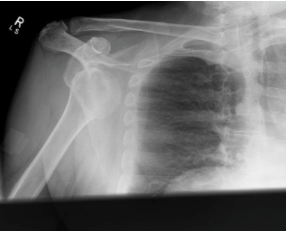

Describe X Ray - what else might be associated on x ray?

i) Anterior dislocation of humerus (Adducted and externally rotated)

Hill - Sachs lesion - Fracture of humeral head as it is impacted against glenoid

Bankart lesion - Fracture of the glenoid labrum as humerus presses against labrum

Methods of shoulder reduction

1) Milch - Supine. Abduct - external rotate - thumb pressure to humeral head

2) Kocher - Adduct arm. Flex elbow. Traction on humerus. External rotation and then forward flexion+internal rotation

3) Stimson - prone on bed. gentle traction with weight over 15-20 minutes

4) Hippocratic - Countertraction in axilla. Humerul traction with in/ext rotation

ii) Management:

History + Examine NV Status

Consent

Analgaesia (Gas/Sedative)

Inline downward traction + Countertraction (with/without internal or external rotation)

Polysling for 2-4 weeks